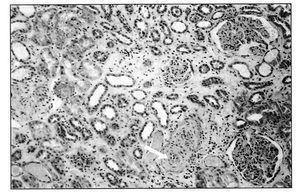

La biopsia renal (BR) demostró 18 glomérulos que presentaban afectación difusa de carácter isquémico con retracción y replegamiento de la pared capilar en las técnicas del PAS y argénticas, y rarefacción de la matriz mesangial. No se evidenció proliferación extracapilar. El intersticio presentaba fibroedema leve con infiltrado por células redondas, con atrofia tubular y cambios regenerativos del epitelio. Los vasos extraglomerulares de pequeño y mediano calibre presentaban cambios de arteriolopatía severa, necrosis fibrinoide de la pared y trombos fibrinoides intraluminales. La inmunofluorescencia fue negativa. Todo ello era compatible con HTA maligna (figura 2, figura 3 y figura 4).

Figura 3. Biopsia renal.